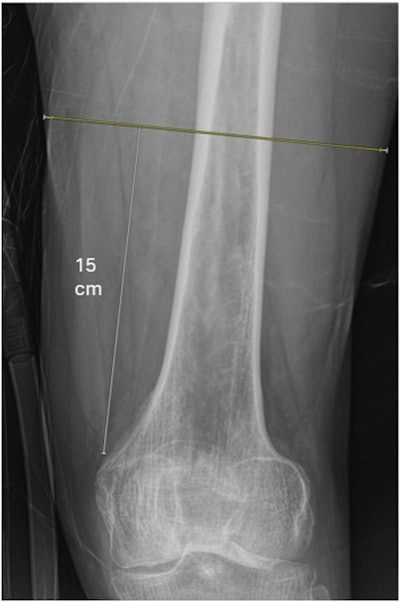

Example of how thigh muscle diameter measurements were obtained from the anteroposterior radiograph. Diameter of thigh muscle (yellow line) and diameter of whole soft tissue envelope (yellow + white lines) were measured 15 cm proximal to the adductor tubercle.Example of how thigh muscle diameter measurements were obtained from the anteroposterior radiograph. Diameter of thigh muscle (yellow line) and diameter of whole soft tissue envelope (yellow + white lines) were measured 15 cm proximal to the adductor tubercle.JBJS Open AccessThe one-year mortality for the group was 22%. Specifically, four patients (2%) died during hospitalization and 10 patients (5%) died within 30 days of admission. The median length of stay was five days, with most patients (n = 163) being discharged to skilled nursing facilities, the authors noted.